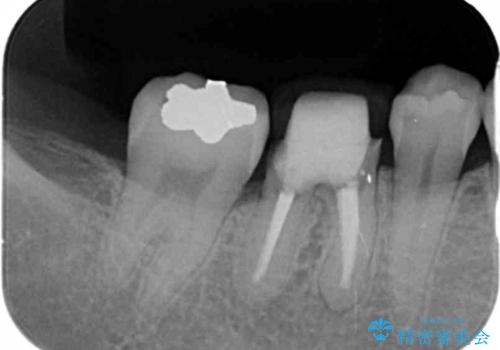

- 治療途中の歯を3年放置した結果、ファイバーコア下に虫歯が再発し抜歯を余儀なくされました。

最終的なクラウンを入れずコアのまま、仮歯のまま長期間過ごすと虫歯が再発し残すことが難しくなってしまうことがあります。